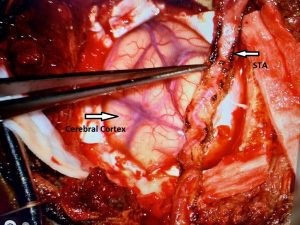

Noninvasive vascular imaging was sufficiently suggestive to warrant conventional digital subtraction angiography, performed by Dr. Brisman and confirming Moya-Moya syndrome (Figures 1). CT Perfusion (Figure 2) showed a decreased transit time of blood to the right hemisphere and the patient was recommended to undergo cerebral revascularization to avert stroke.

Figure 3

A right sided Encephaloduroarteriosynagios (EDAS) procedure was undertaken in which the right superficial temporal artery (STA) is sewn (synangiosed) to the pia in an effort to generate vascular arborization and increased blood flow to the hemisphere (Figure 3).